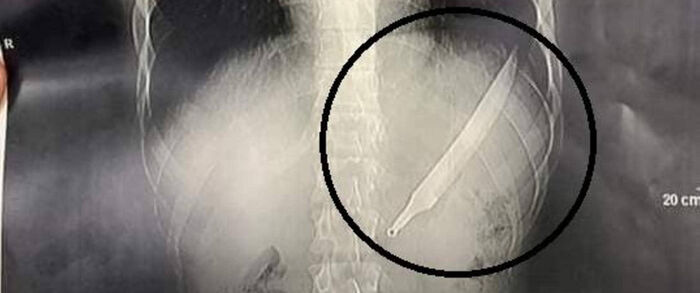

مصري يبتلع سكينا طوله 27 سنتيمترا.. والأطباء يصنعون معجزة